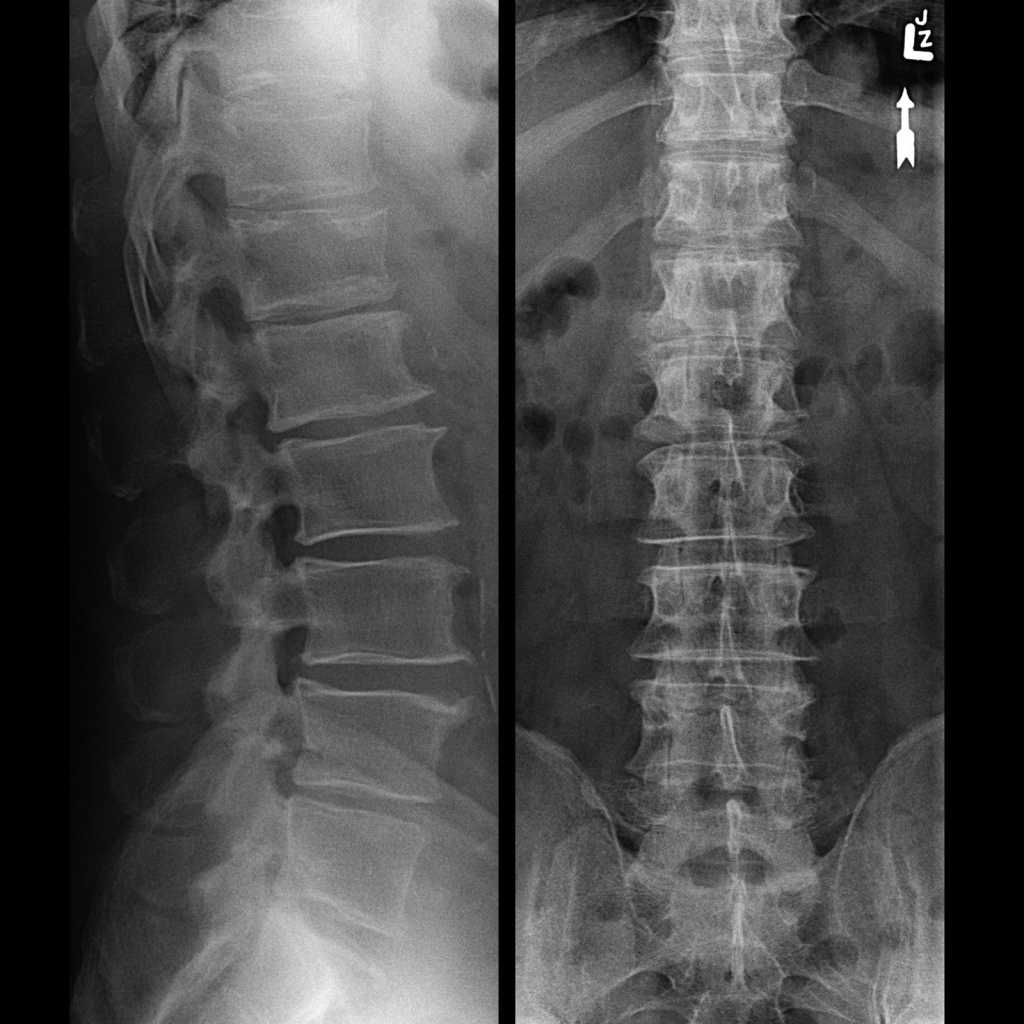

Рентген шейных позвонков при спина бифида

Раздел: Фотозарисовки